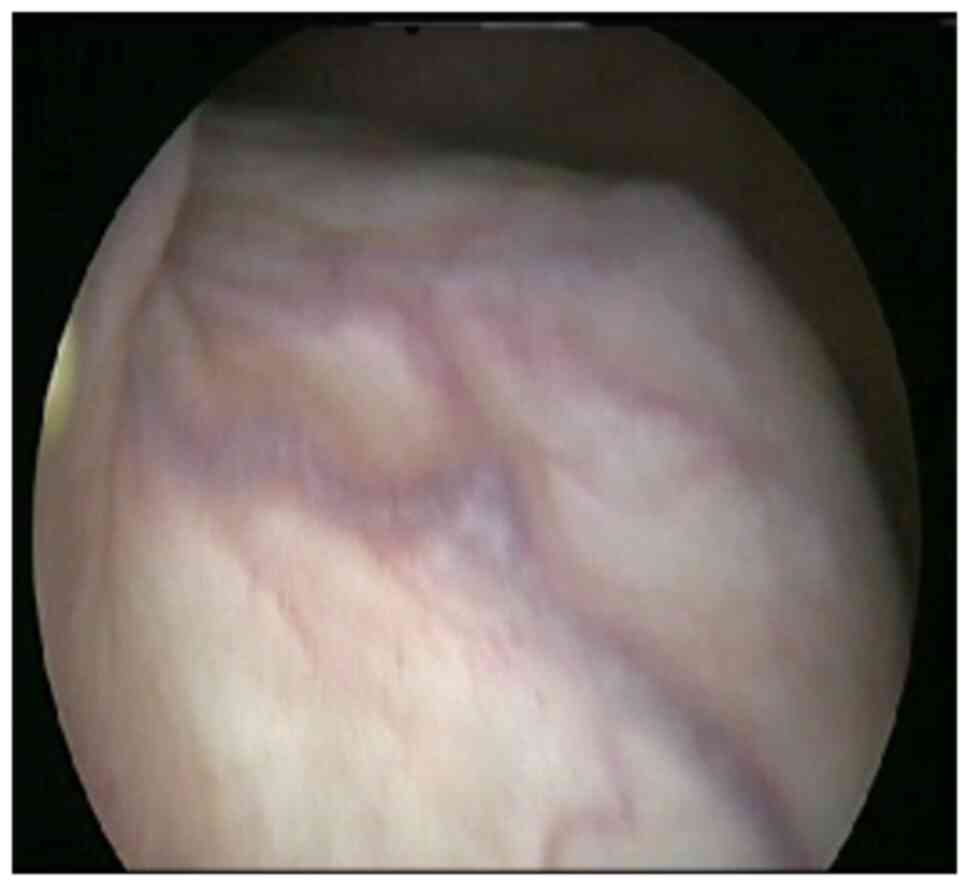

Bladder leiomyoma in the absence of symptoms: A case report and mini‑review of the literature

Figure 2